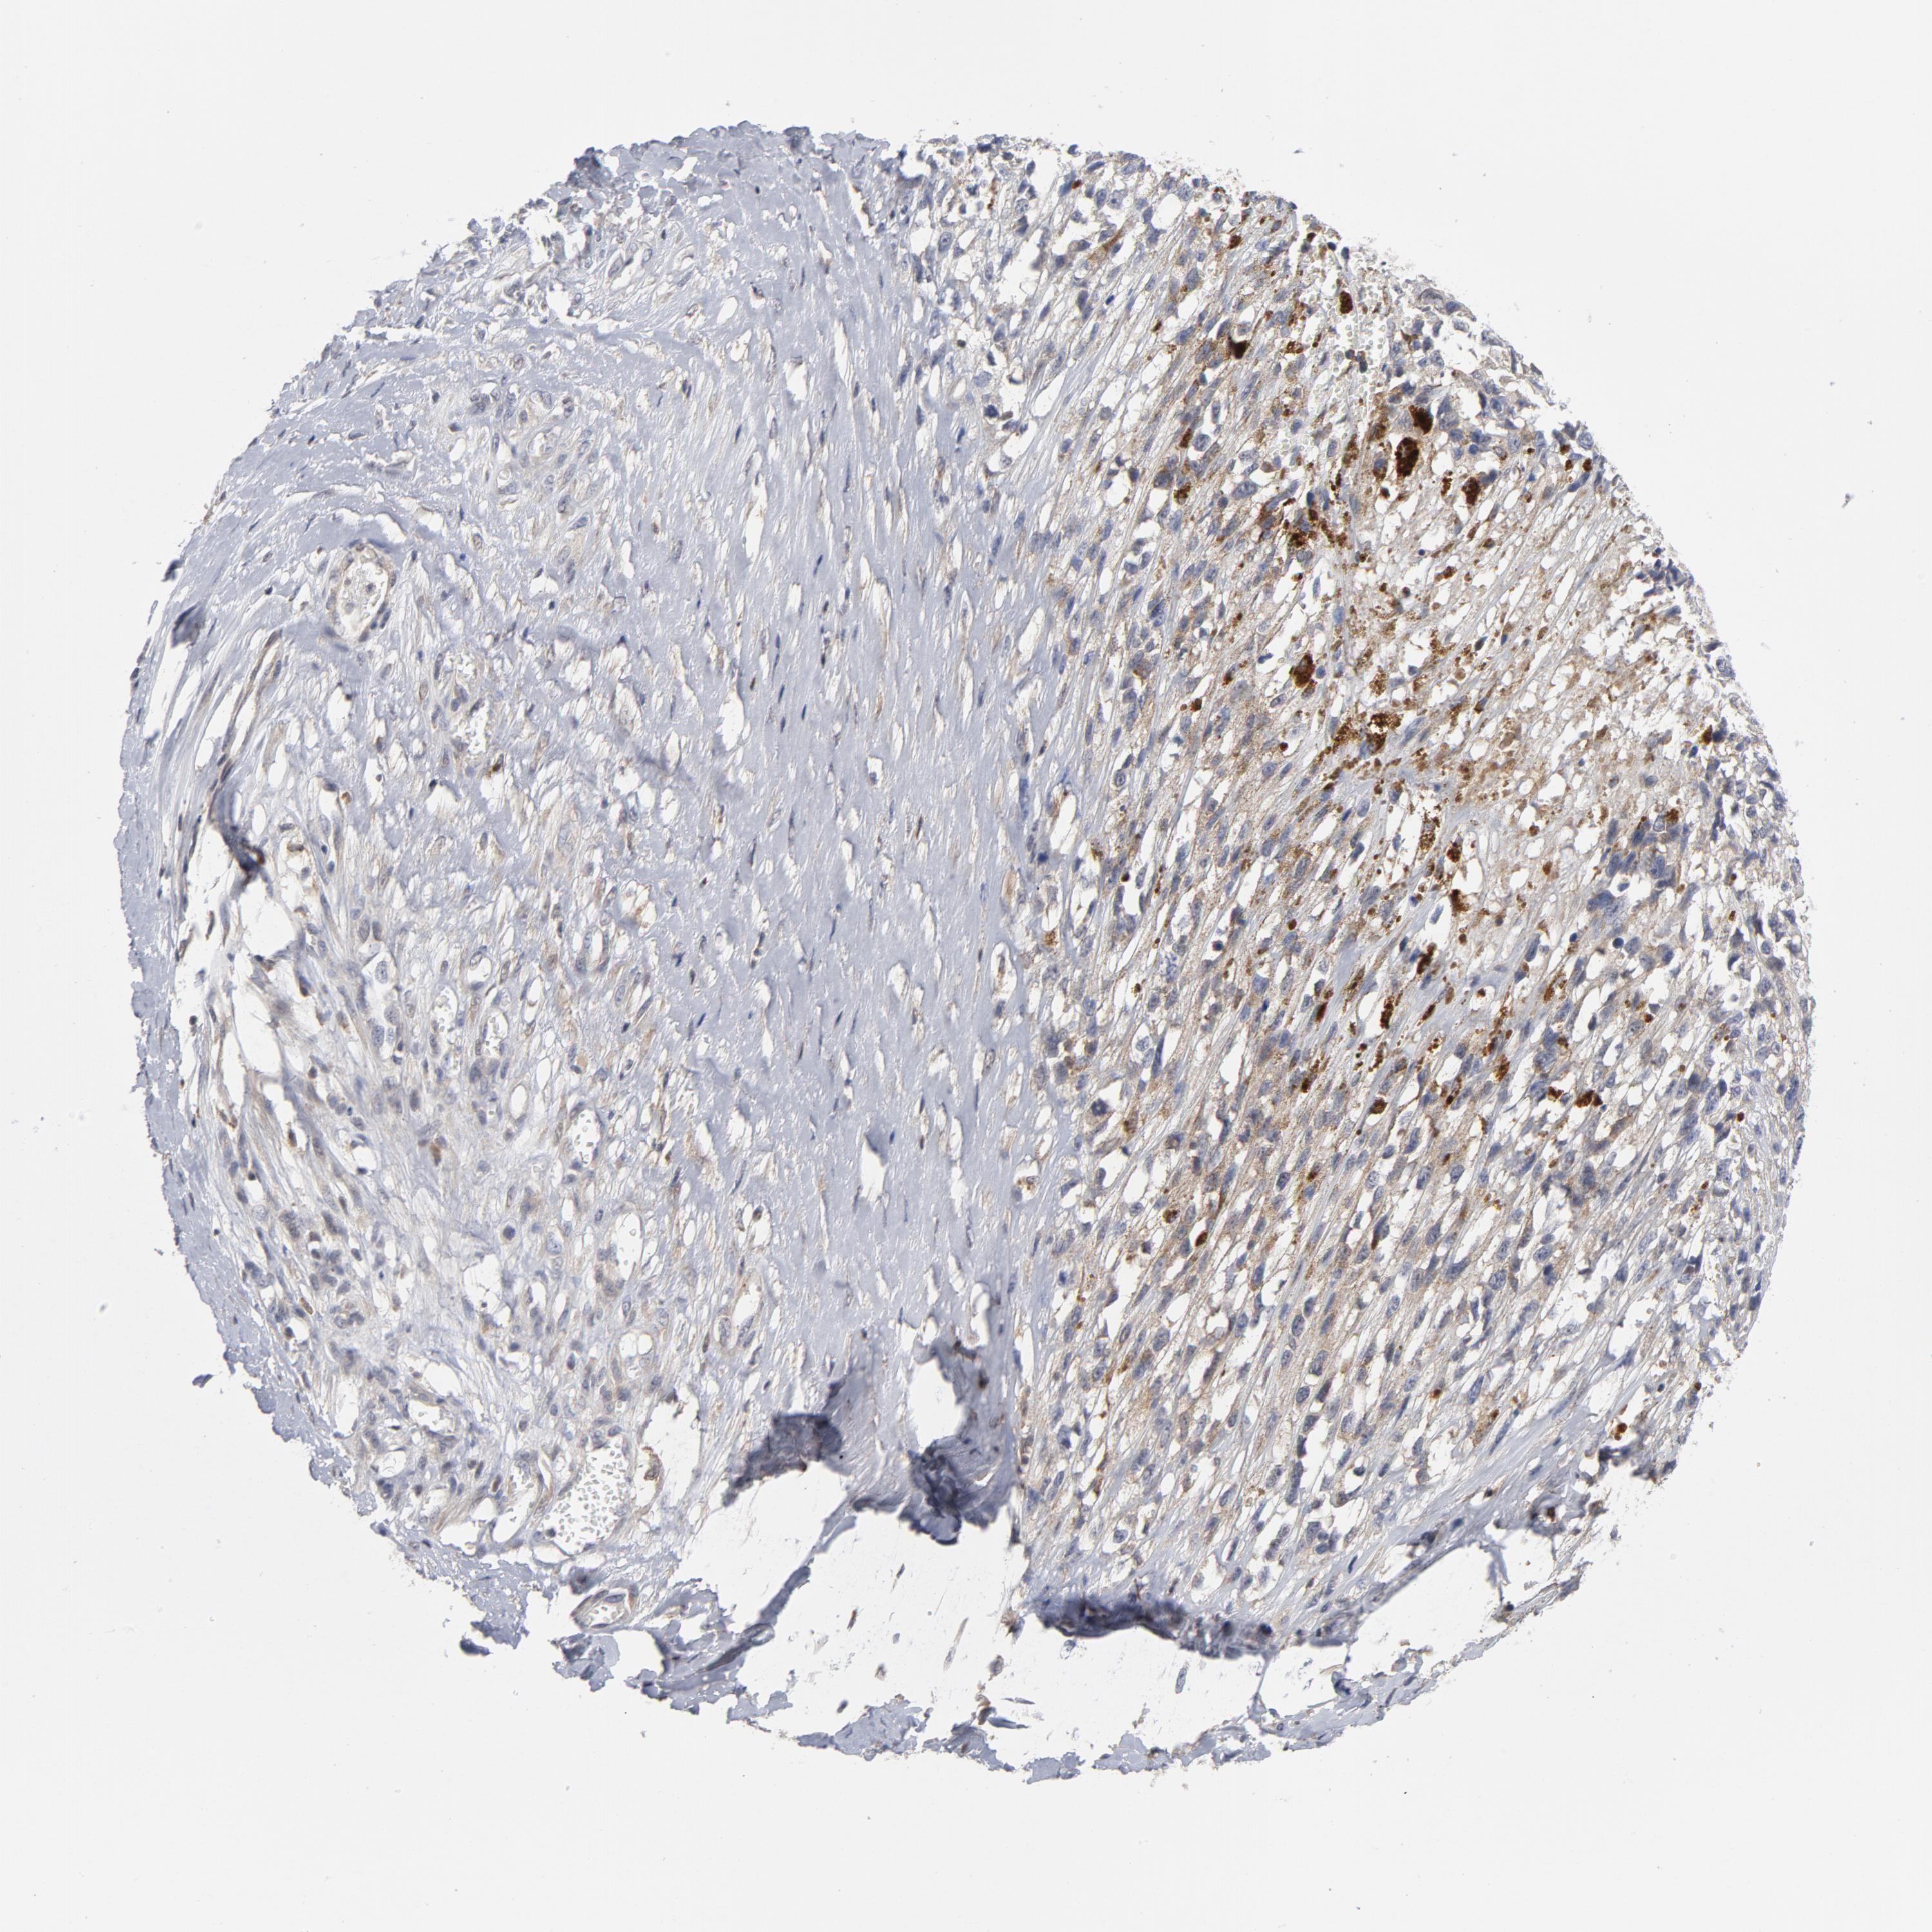

MELANOMA - Protein expressioni

A mouse-over function shows sample information and annotation data. Click on an image to view it in a full screen mode. Samples can be filtered based on level of antibody staining by selecting one or several of the following categories: high, medium, low and not detected. The assay and annotation is described here.

Antibody stainingi

Antibody staining in the annotated cell types in the current human tissue is reported as not detected, low, medium, or high, based on conventional immunohistochemistry profiling in selected tissues. This score is based on the combination of the staining intensity and fraction of stained cells.

Each image is clickable and will lead to virtual microscopy that enables deeper exploration of all samples and also displays staining intensity scores, fraction scores and subcellular localization as well as patient and tissue information for each sample.

Antibody HPA071341

Antibody CAB004602

Staining

High

Medium

Low

Not detected

Intensity

Strong

Moderate

Weak

Negative

Quantity

>75%

75%-25%

<25%

None

Location

Nuclear

Cytoplasmic/membranous

Cytoplasmic/membranous,nuclear

Malignant melanoma, NOS

Malignant melanoma, Metastatic site